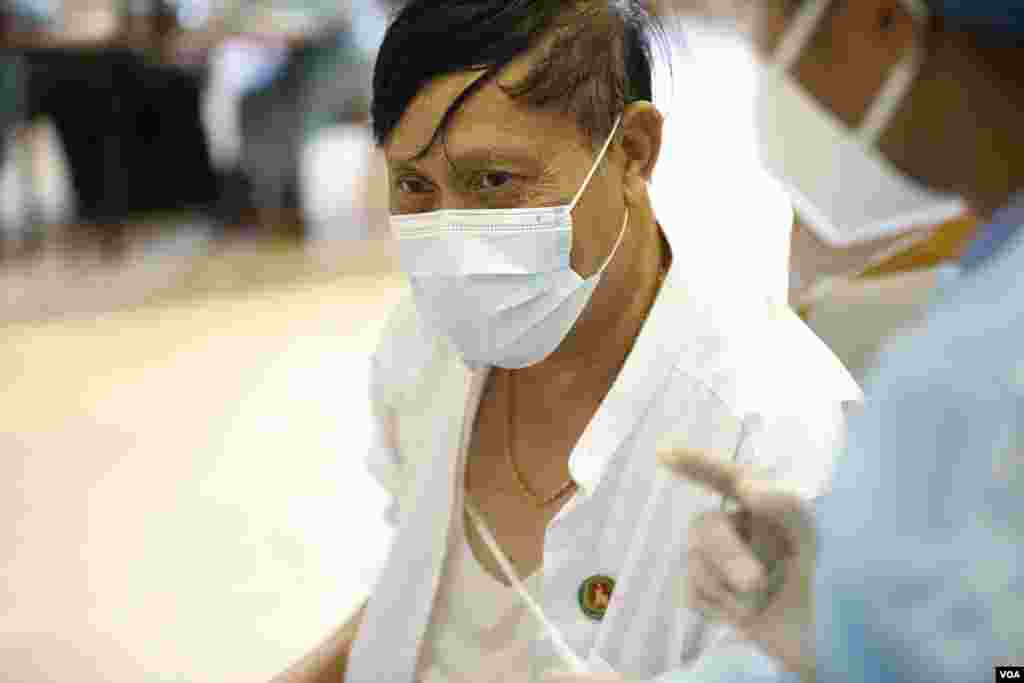

လွှတ်တော် တက်ရောက်မည့် ပြည်သူ့လွှတ်တော် ကိုယ်စားလှယ်များကို COVID ကာကွယ်ဆေး စတင် ထိုးနှံသည့် မြင်ကွင်းတချို့။

လှှတျတောျ တကျရောကျမည့ျ ပွညျသူ့လှှတျတောျ ကိုယျစားလှယျမြားကို COVID ကာကှယျဆေး စတငျ ထိုးနှံသည့ျ မွငျကှငျးတခြို့။

လှှတျတောျ တကျရောကျမည့ျ ပွညျသူ့လှှတျတောျ ကိုယျစားလှယျမြားကို COVID ကာကှယျဆေး စတငျ ထိုးနှံသည့ျ မွငျကှငျးတခြို့။